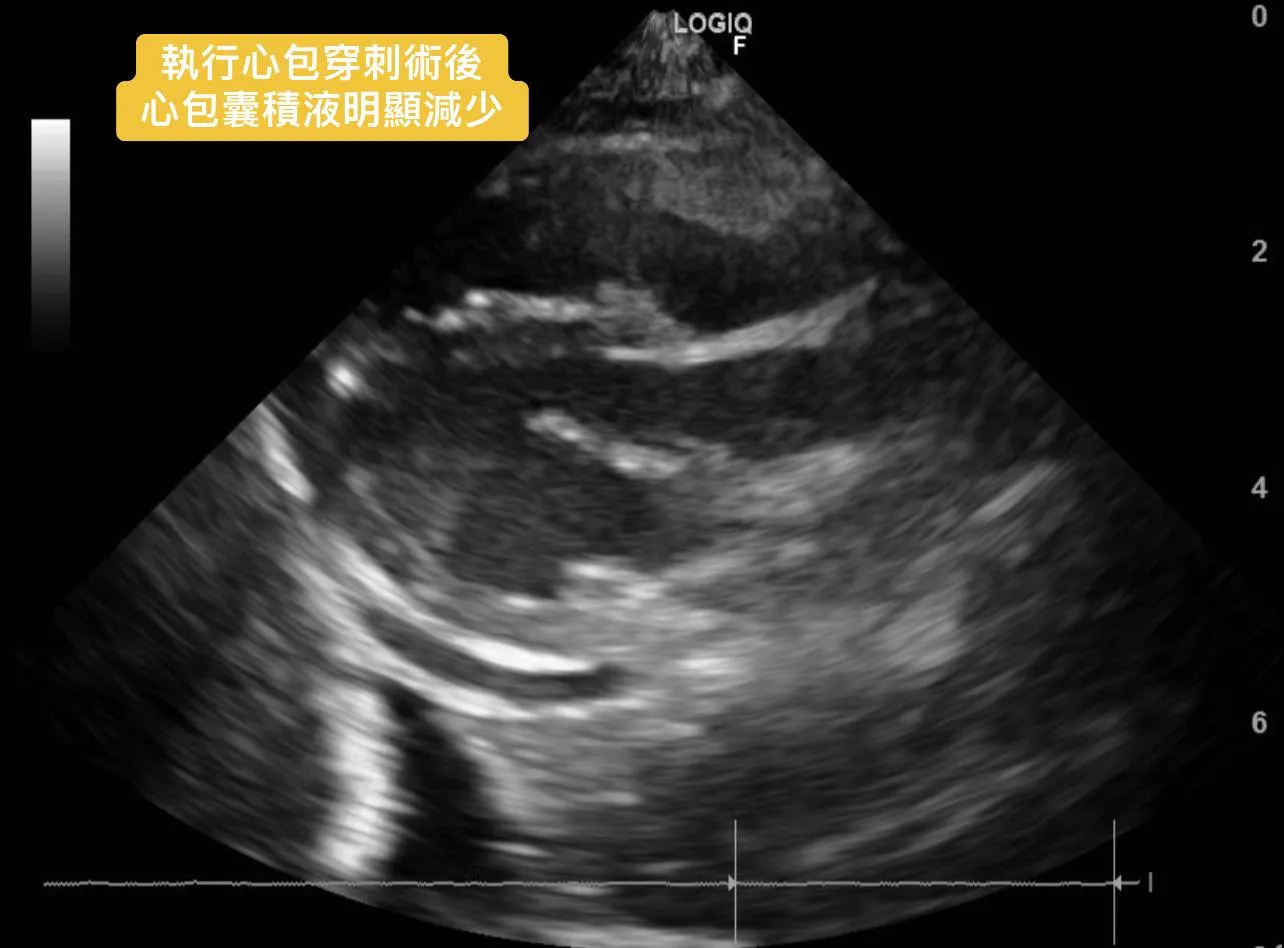

3. 心臟超音波檢查發現「大量心包囊積液」。

心包穿刺術後,毛孩立即改善喘的問題。

一週後回診時,毛孩精神食慾正常,不會喘與咳嗽,心包囊與腹水狀況也改善許多。